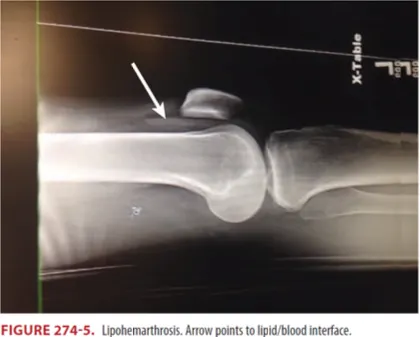

Lateral view

X-ray 상 보이는 fat fluid level (lipohemarthrosis)는 intra-articular fracture 의미(white arrow)

→ Aspiration 시 발견된 혈액과 지방입자는 lipohemarthrosis의 특징적인 소견이며 intra-articular

knee fracture를 시사